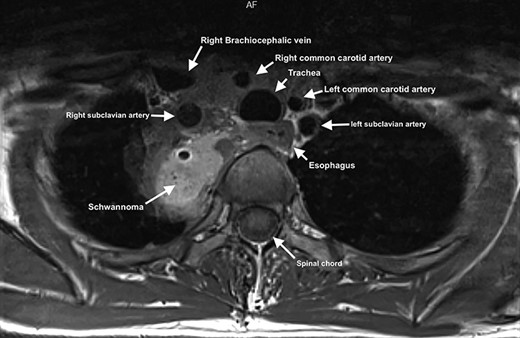

A 58-year-old female smoker with a history of cosmetic surgery complained of a large supraclavicular cervical mass associated with some neurological disorders (including anisocoria and ptosis of the right eyelid) since 2014. An ultrasound of the neck with cytological examination raised the suspicion of ‘Schwannoma’ with liquid content. Computed tomography (CT) of the neck and chest confirmed the presence of a 6.6 × 6 cm paracervical and paramediastinal right mass that dislocated the trachea and esophagus. The injury was also confirmed by nuclear magnetic resonance imaging (MRI) of the neck and chest (Figs 1, 2).

MRI showing paravertebral neurinoma with liquid content (C7-D3) with right intrathoracic involvement compressing the mediastinal structures without signs of vascular infiltration.